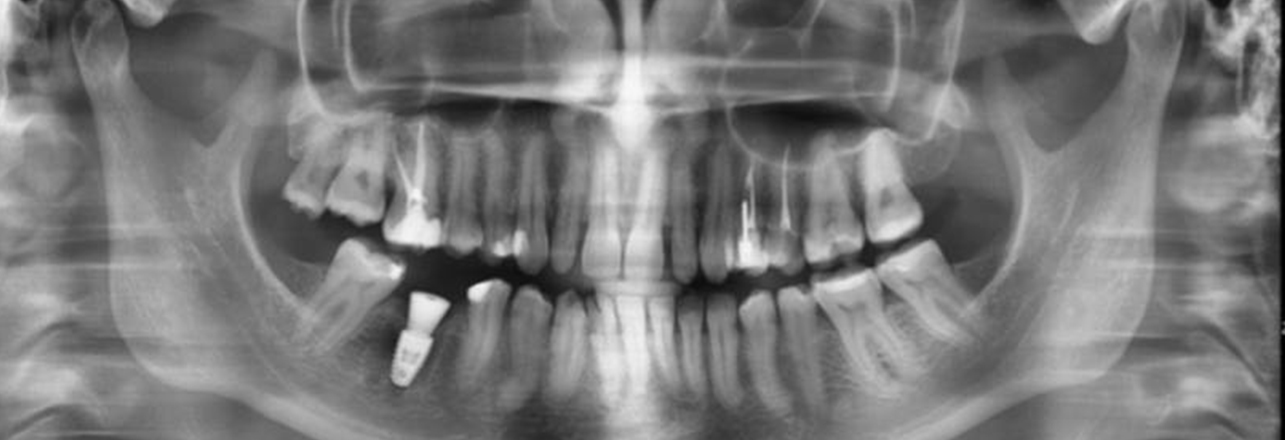

Пациент обратился к Егору Алексеевичу с проблемой — разрушение коронковой части зуба и воспалением. Перелечивание и ортопедическое восстановление в данном случае были невозможны — принято решение об удалении с одномоментной имплантацией.

3. Аугментация лунки ксеногенным костным материалом Bio-Oss

4. Установка имплантата Straumann BLT 4,8 × 8 мм

bujhmm.jpg Зафиксирована коронка с учётом всех функциональных и эстетических требований.

Теперь зуб полноценно участвует в жевании и визуально не отличается от остальных!